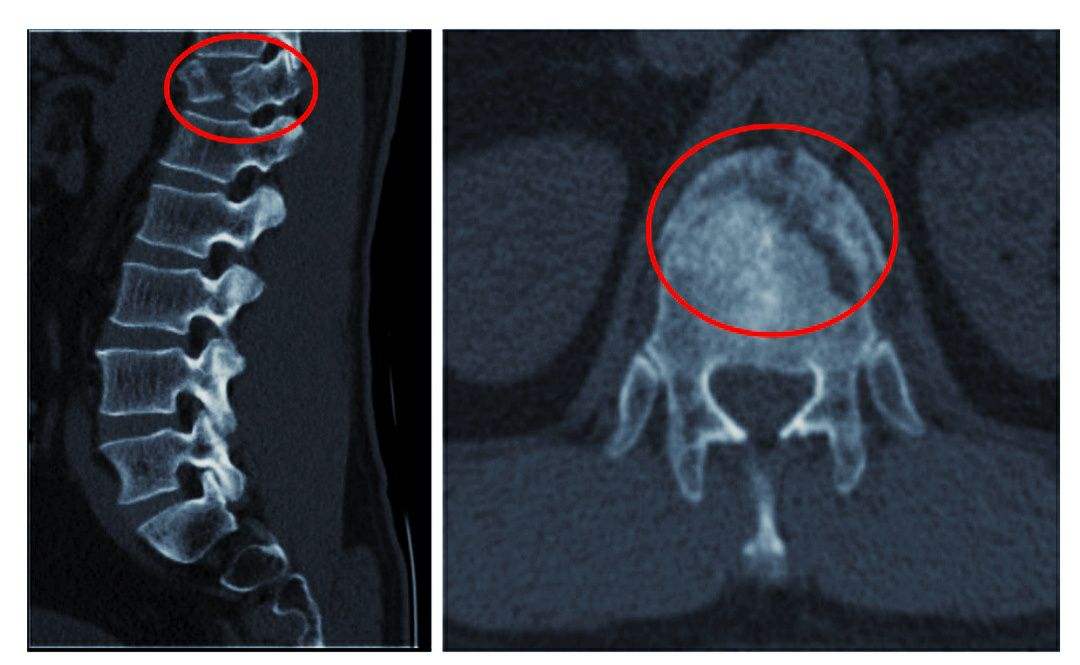

5、頸椎骨折

由于頸椎骨折,可造成出血,水腫,或碎骨片移位波及到椎間孔或椎管,直接壓迫頸神經(jīng)根或頸脊髓。骨癡的形成,使椎管、椎間孔發(fā)生狹窄性改變,產(chǎn)生脊髓、神經(jīng)根的受壓癥狀。